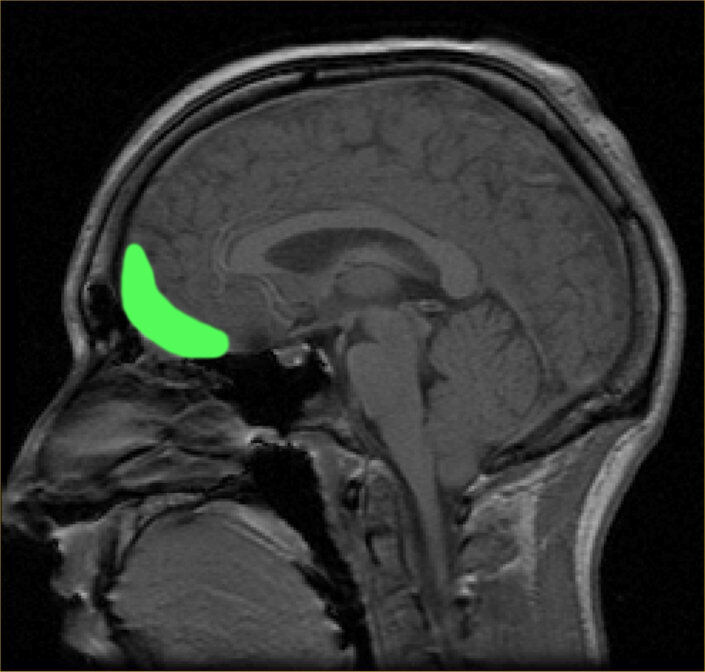

Вентральная область покрышки (VTA, зеленая область) —  начало мезокортикального и мезолимбического дофаминовых путей.